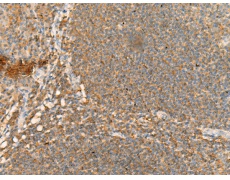

IHC positive control: |

Human esophagus cancer |

IHC Recommend dilution: |

40-200 |